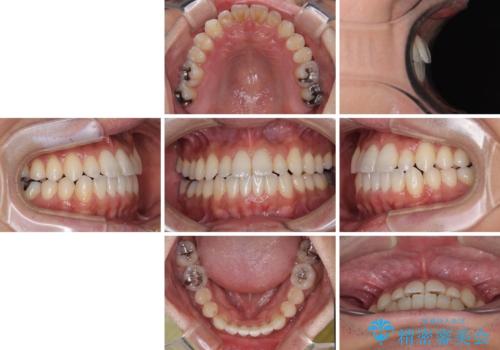

内側に引っ込んだ歯を治したい インビザラインの矯正治療

上下顎ともに歯列全体の側方拡大とIPR(歯と歯の間を削る)によってデコボコとクロスバイトが解消するように設計し、インビザラインにより治療を行うこととしました。

反対咬合特有の治療途中の前歯の干渉が長く続き、治療中に食事をとりにくく、ご迷惑をおかけしました。

前歯の咬み合わせの調整などを行い、安定した咬み合わせに仕上げることができました。